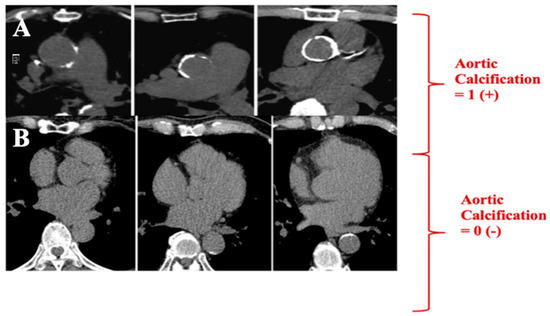

| Thorax CT—aortic calcification +, n (%) | 86 (%82.7) | 103 (%46.6) | <0.001 |

| Thorax CT CAC + aortic calcification + | 5.28 | 3.13–8.91 | <0.001 | 3.85 | 1.69–8.78 | 0.001 |

| C | CACS + Aort calcification + | 1 point |